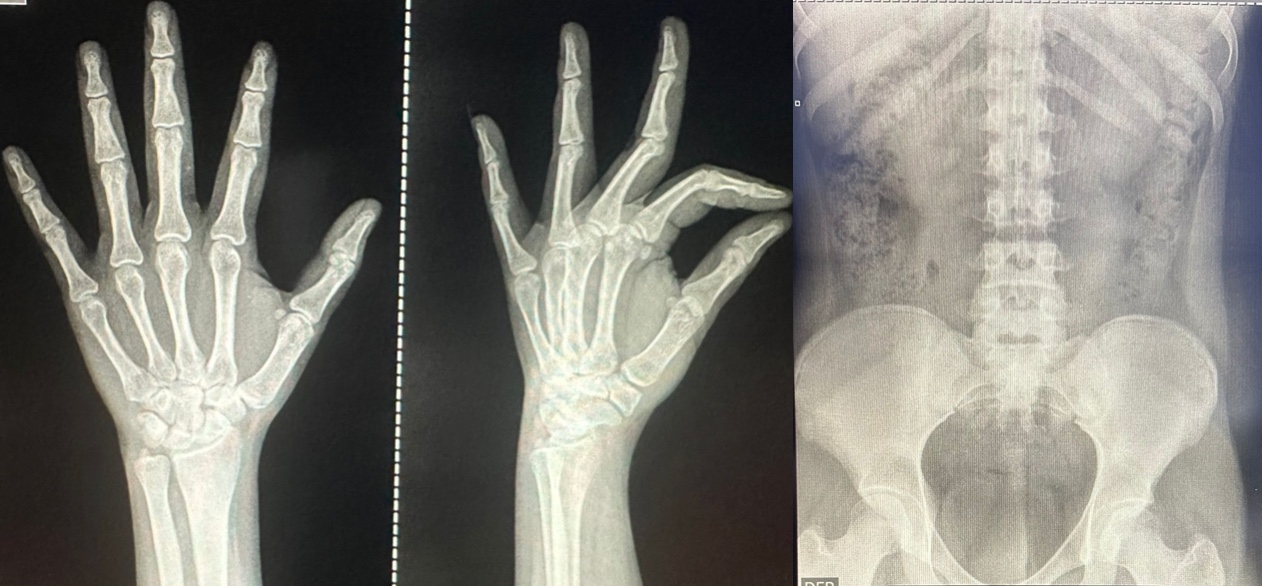

En nuestro hospital, ponemos a tu disposición una amplia gama de servicios de diagnóstico por imagen diseñados para ofrecer precisión y rapidez en la detección y monitoreo de tu salud. Contamos con tecnologías avanzadas y personal altamente capacitado para realizar tomografías, rayos X, ultrasonidos, mamografías y electrocardiogramas.